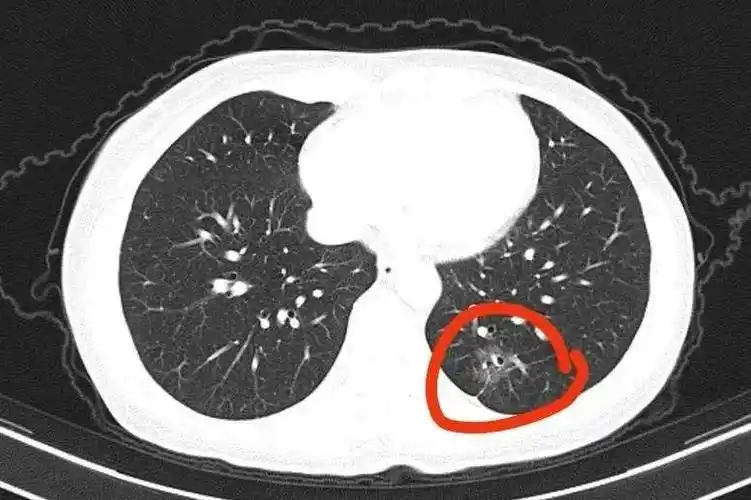

典型吸烟导致肺癌的ct图像,2.9cm肺结节,有毛刺,分叶, - 抖音

低剂量ct肺癌筛查检出肺癌的影像特征

看不懂ct图像?各种类型肺癌典型表现!